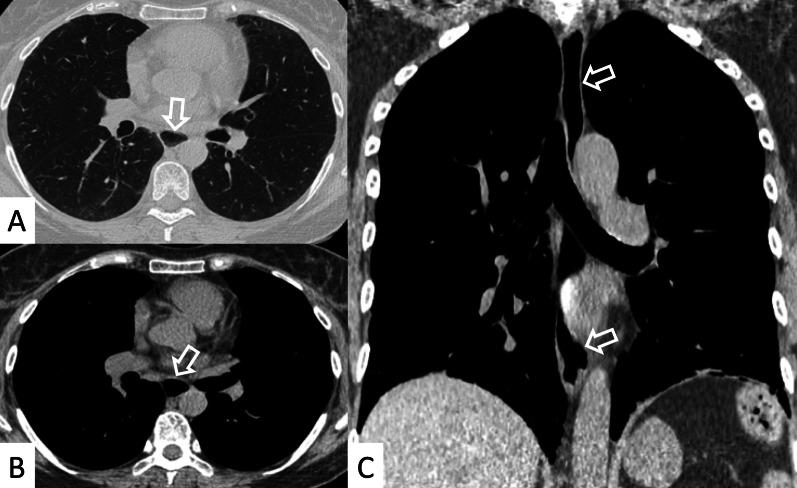

Connective tissue diseases (CTDs) include a spectrum of disorders that affect the connective tissue of the human body; they include autoimmune disorders characterized by immune-mediated chronic inflammation and the development of fibrosis. Lung involvement can be misdiagnosed, since pulmonary alterations preceded osteo-articular manifestations only in 20% of cases and they have no clear clinical findings in the early phases. All pulmonary structures may be interested: pulmonary interstitium, airways, pleura and respiratory muscles. Among these autoimmune disorders, rheumatoid arthritis (RA) is characterized by usual interstitial pneumonia (UIP), pulmonary nodules and airway disease with air-trapping, whereas non-specific interstitial pneumonia (NSIP), pulmonary hypertension and esophageal dilatation are frequently revealed in systemic sclerosis (SSc). NSIP and organizing pneumonia (OP) may be found in patients having polymyositis (PM) and dermatomyositis (DM); in some cases, perilobular consolidations and reverse halo-sign areas may be observed. Systemic lupus erythematosus (SLE) is characterized by serositis, acute lupus pneumonitis and alveolar hemorrhage. In the Sjögren syndrome (SS), the most frequent pattern encountered on HRCT images is represented by NSIP; UIP and lymphocytic interstitial pneumonia (LIP) are reported with a lower frequency. Finally, fibrotic NSIP may be the interstitial disease observed in patients having mixed connective tissue diseases (MCTD). This pictorial review therefore aims to provide clinical features and imaging findings associated with autoimmune CTDs, in order to help radiologists, pneumologists and rheumatologists in their diagnoses and management.

结缔组织病(CTDs)包括一系列影响人体结缔组织的疾病;它们包括以免疫介导的慢性炎症和纤维化发展为特征的自身免疫性疾病。肺部受累可能会被误诊,因为肺部改变仅在20%的病例中先于骨关节炎表现出现,且在早期阶段没有明确的临床发现。所有肺部结构都可能受累:肺间质、气道、胸膜和呼吸肌。在这些自身免疫性疾病中,类风湿关节炎(RA)的特征是普通型间质性肺炎(UIP)、肺结节和伴有空气潴留的气道疾病,而系统性硬化症(SSc)常表现为非特异性间质性肺炎(NSIP)、肺动脉高压和食管扩张。NSIP和机化性肺炎(OP)可见于多发性肌炎(PM)和皮肌炎(DM)患者;在某些情况下,可观察到小叶周围实变和反晕征区域。系统性红斑狼疮(SLE)的特征是浆膜炎、急性狼疮性肺炎和肺泡出血。在干燥综合征(SS)中,HRCT图像上最常见的表现是NSIP;UIP和淋巴细胞间质性肺炎(LIP)的报道频率较低。最后,纤维化NSIP可能是混合性结缔组织病(MCTD)患者中观察到的间质性疾病。因此,本图像综述旨在提供与自身免疫性CTDs相关的临床特征和影像学表现,以帮助放射科医生、呼吸科医生和风湿病科医生进行诊断和管理。